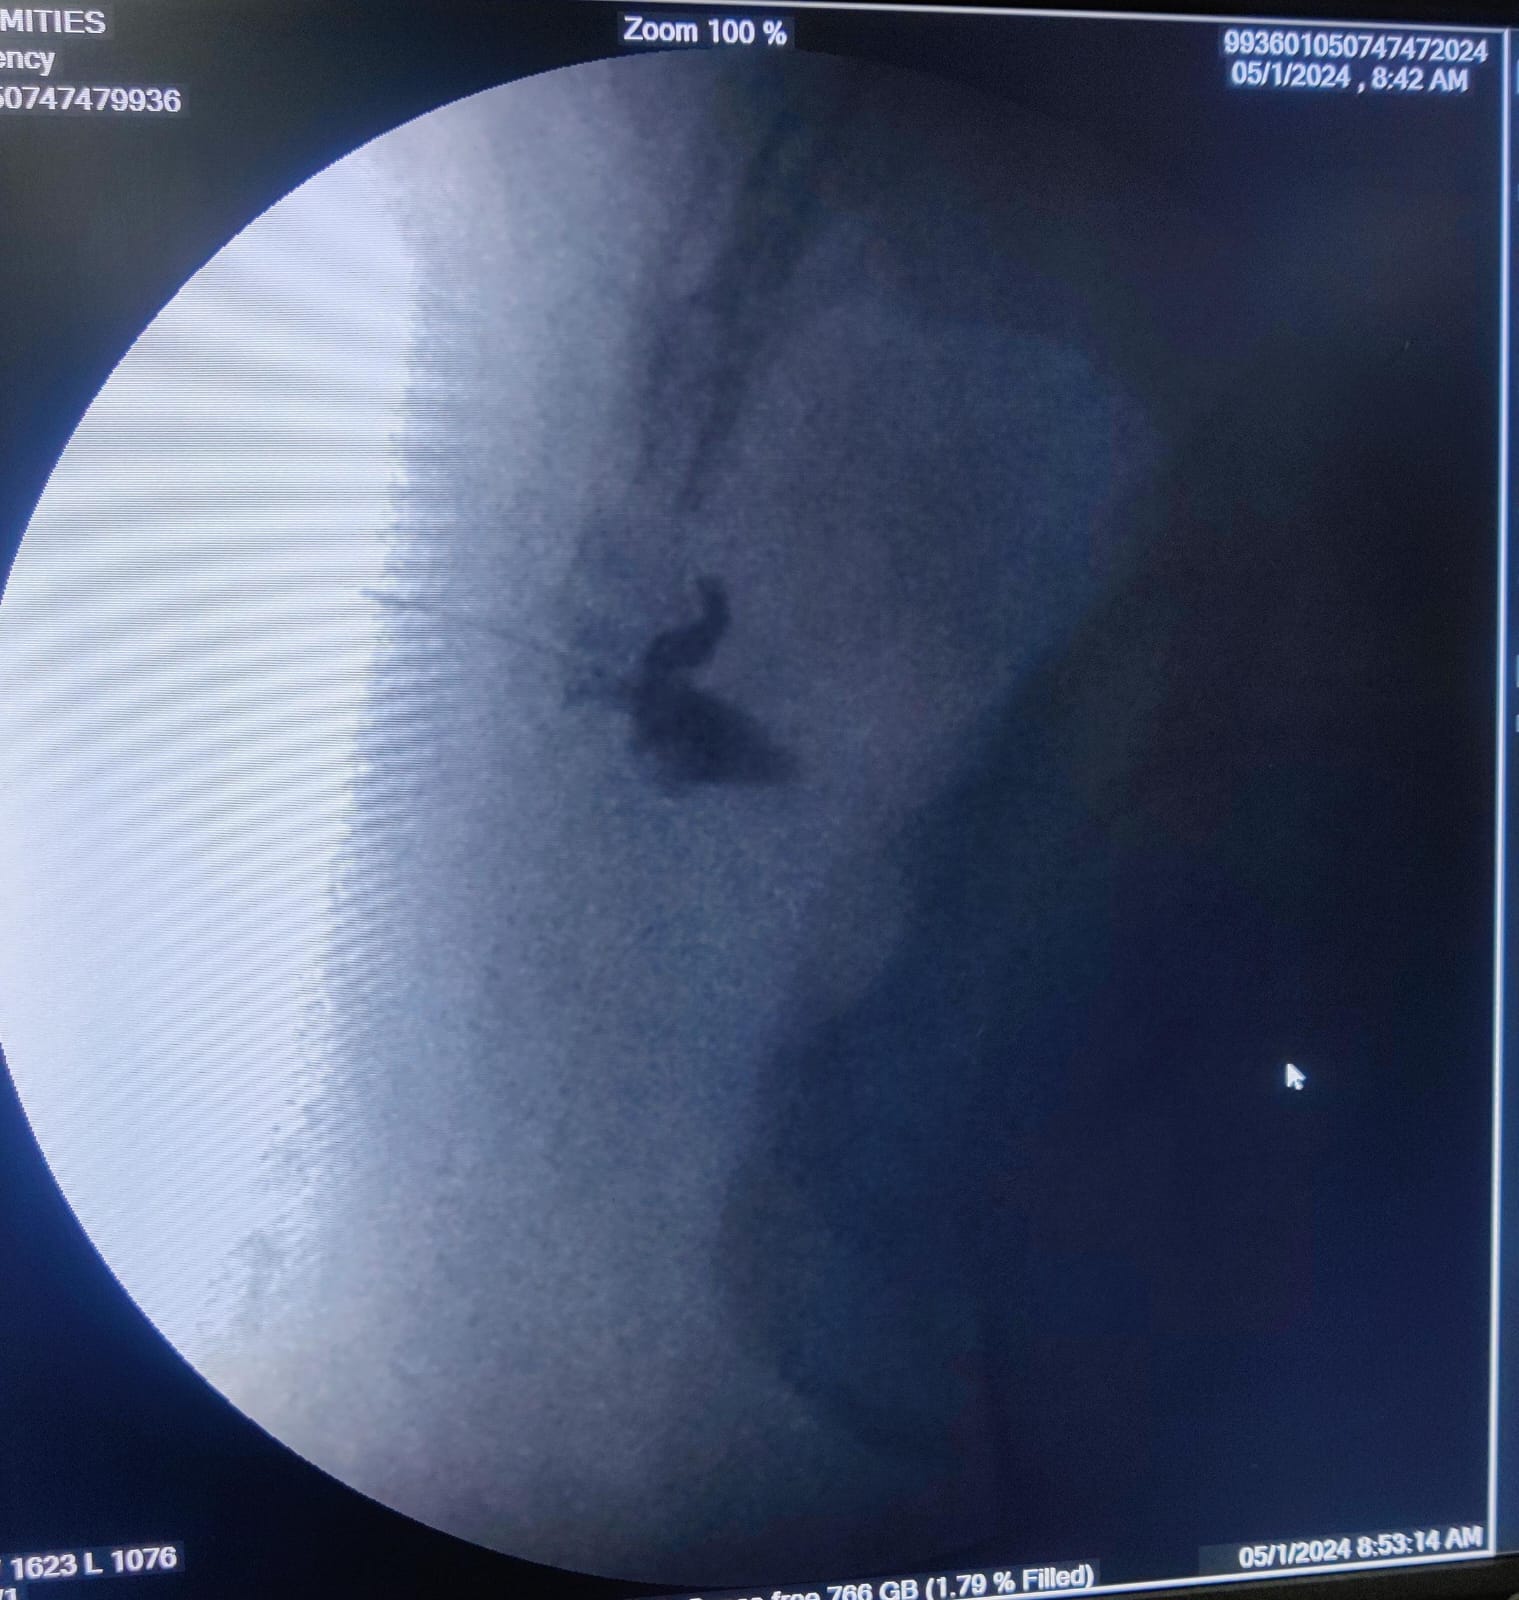

are you looking for coccydynia doctor in Pune? Are you looking for coccyx pain/ tailbone pain specialist in Pune? Are you looking for best spine specialist in Pune? Ganglion Impar Radiofrequency Ablation (RFA) for Coccydynia: A Promising Intervention for Tailbone Pain Coccydynia, or pain in the coccyx, can be a debilitating condition that significantly impacts the quality of life for those affected. The coccyx, also known as the tailbone, is a small triangular bone at the base of the spine. Coccydynia can result from various causes, such as trauma, inflammation, or degenerative changes. For those who have not found relief through conservative treatments, a minimally invasive procedure known as Ganglion Impar Radiofrequency Ablation (RFA) has emerged as a promising intervention. Understanding Coccydynia Coccydynia often manifests as localized pain at the tailbone, making sitting and certain movements extremely uncomfortable. Trauma, such as a fall or childbirth, is a common trigger for coccydynia. Inflammatory conditions, infections, and degenerative changes in the coccyx area can also contribute to the development of this condition. Conservative Treatments and Their Limitations Initial approaches to managing coccydynia typically involve conservative measures, including: 1. Pain Medications: Over-the-counter or prescription medications may be used to alleviate pain and reduce inflammation. 2. Physical Therapy: Targeted exercises and stretches can help improve flexibility and reduce discomfort. 3. Cushions and Posture Modification: Using special cushions or making adjustments to sitting posture can provide relief. Despite these efforts, some individuals continue to experience persistent coccydynia, prompting the exploration of more advanced interventions. Ganglion Impar, also known as the Walther's Ganglion, is a small bundle of nerves located near the coccyx. It plays a crucial role in transmitting pain signals from the pelvic region. Ganglion Impar Radiofrequency Ablation (RFA) is a minimally invasive procedure that targets and disrupts the nerve signals responsible for transmitting pain. During Ganglion Impar RFA, a specialized needle is precisely guided under sonography or X-ray guidance to the ganglion. Once in position, radiofrequency energy is applied to the ganglion, creating a heat lesion. This heat lesion disrupts the transmission of pain signals, providing relief from coccydynia. Advantages of Ganglion Impar RFA 1. Minimally Invasive: Ganglion Impar RFA is performed through a needle, minimizing tissue damage and reducing the risk of complications compared to more invasive surgical procedures. 2. Targeted Pain Relief: By specifically targeting the ganglion responsible for transmitting pain signals, this procedure offers focused relief to the affected area. 3. Outpatient Procedure: Ganglion Impar RFA is typically performed on an outpatient basis, allowing patients to return home the same day.